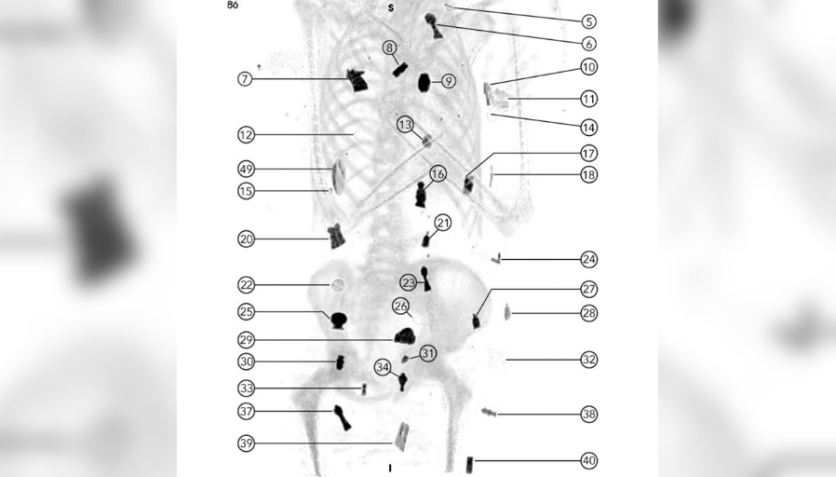

Os pesquisadores descobriram os amuletos colocados sobre o corpo e dentro do corpo do “menino dourado” mumificado ao usar tomografia computadorizada para desembrulhar digitalmente os restos, sem perturbá-los.

Ao escanear a múmia, os pesquisadores detectaram 49 amuletos com 21 desenhos diferentes, incluindo uma língua dourada colocada dentro da boca e um escaravelho em forma de coração dourado localizado no peito, que os antigos egípcios acreditavam que poderia ajudar na transição para a vida após a morte.

“Demonstramos que o corpo dessa múmia foi extensivamente decorado com 49 amuletos, estilizados lindamente em um arranjo único de três colunas entre as dobras dos invólucros e dentro da cavidade do corpo da múmia. Eles incluem o Olho de Horus, o escaravelho, o amuleto de Akhet do horizonte, a placenta e o nó de Isis, e outras peças", disse o autor do estudo, doutor Sahar Saleem, professor da Faculdade de Medicina da Universidade do Cairo, em um comunicado.

"Muitas eram feitas de ouro, e há também pedras semipreciosas, argila queimada e faiança. O objetivo delas era proteger o corpo e dar-lhe vitalidade na vida após a morte”.

O amuleto de língua dourada colocado na boca do menino foi feito para ajudá-lo a falar na vida após a morte. Um amuleto de nó de Isis significava que a deusa protegeria seu corpo. As peças de falcões e plumas de avestruz representavam os aspectos espirituais e materiais da vida.

Já o amuleto de dois dedos, com a forma dos dedos indicador e médio da mão direita, encontrado na parte inferior do tronco, ajudava a proteger o corte feito para o embalsamento. Por fim, o escaravelho dourado seria usado para ajudar nas dificuldades do submundo.